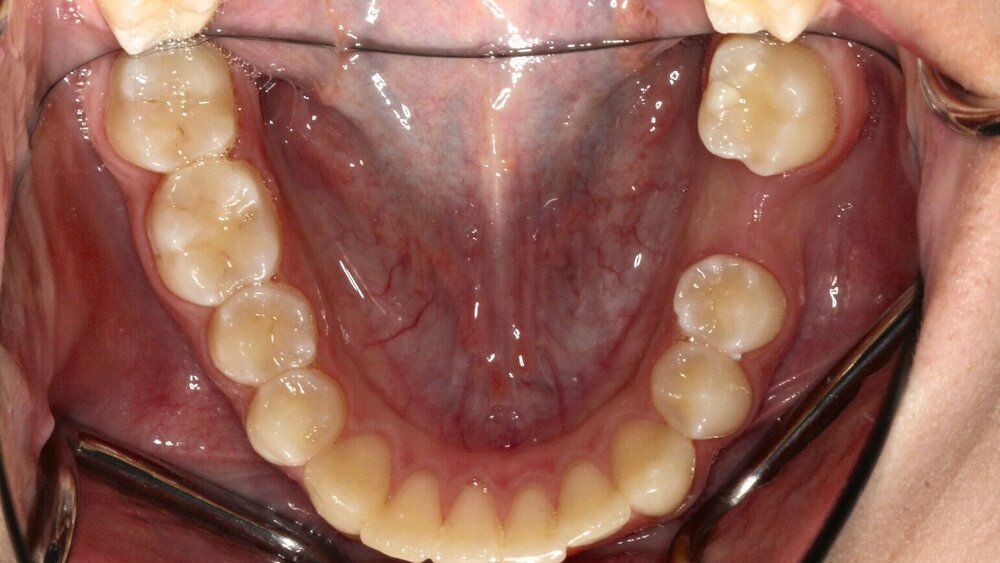

Die Abbildungen 4c bis 4e dokumentieren die Verlaufskontrollen aus den Jahren 2019, 2021 und 2023. Man erkennt eine sehr gute Entwicklung des Zahnbogens und einen spontanen Lückenschluss durch den Zahn 47.